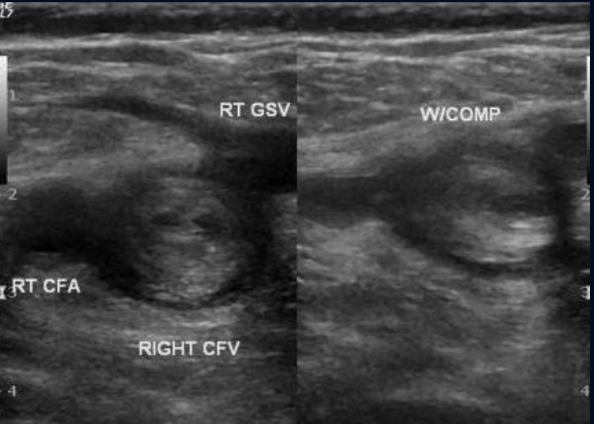

Pathology?

DVT in the Common femoral vein